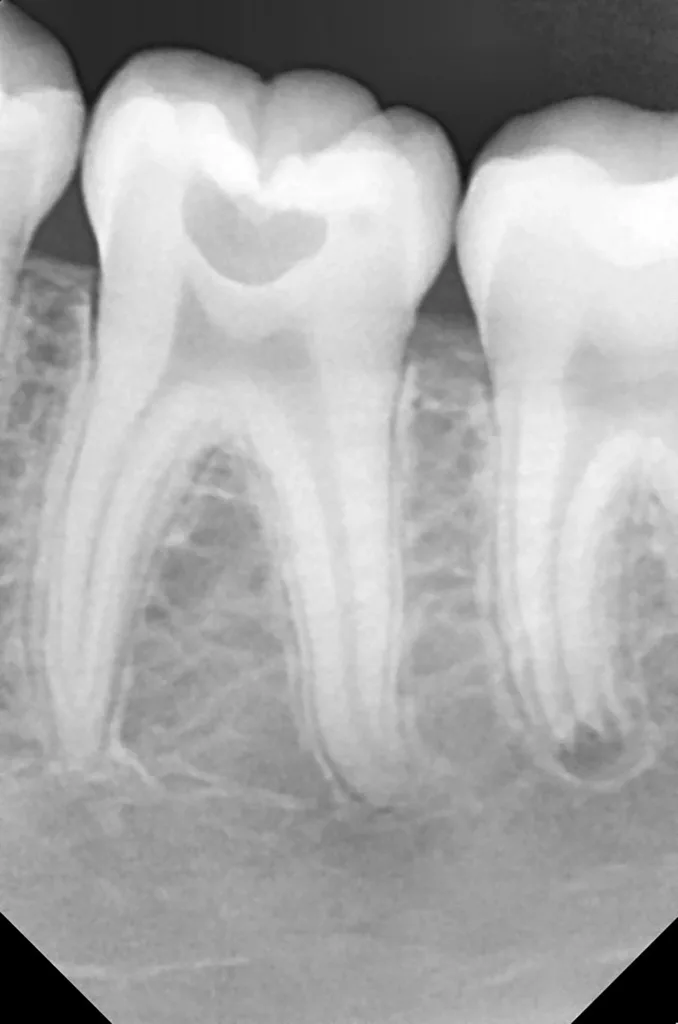

Unter Lokalanästhesie mit dem STA-System (Milestone Scientific, USA) und Septanest 1/200 000 (Septodont, Frankreich) wurde die überstehende Gingiva mit dem Khors Koagulator (Эctatex, Ukraine) koaguliert und der Bereich unter Kofferdam kontaminationsfrei dargestellt (Klammer U67, KSK Dentech, Japan). Die schmalen Fissuren wurden mit dem Fissurenbohrer CD-53F (Mani, Japan) erweitert, um anschließend mittels RONDOflex plus 360 (KaVo Dental, Deutschland) und Pulver 27 µm vollständig gereinigt werden zu können. Es konnte weder durch visuelle Inspektion noch Sondierung mit 0.08 H-file (Mani, Japan) ein Defekt des Zahnschmelzes festgestellt werden. Unter Berücksichtigung der Integrität des Zahnschmelzes, der Symptomlosigkeit, des Behandlungszeitpunktes, Alters des Kindes und Wachstums der Zahnwurzeln fiel gemeinsam mit den Eltern die Wahl auf eine konservative Therapie. Es wurde eine Fissurenversiegelung mit Clinpro Sealant (3M, USA) unter Anwendung eines adhäsiven Behandlungsprotokolls mit Optibond FL (Kerr, USA) durchgeführt. Dieser klinische Fall ist dahingehend einzigartig, da alle anderen ersten und zweiten Molaren des Kindes ebenso von einer PEIR betroffen waren (Grad 1 bis 2 der Läsion nach Seow) (Abb. 3 und 12). Normallerweise ist nur ein Zahn bei einer Patientin oder einem Patienten betroffen. Die Zahnkronen der anderen betroffenen Zähne erwiesen sich bei der klinischen Untersuchung als intakt; die radioluzenten Läsionen innerhalb des koronalen Dentingewebes waren wesentlich kleiner als die von Zahn 36. Daher wurde auch bei diesen Molaren das gleiche Behandlungsprotokoll angewendet und nur eine Fissurenversiegelung durchgeführt.